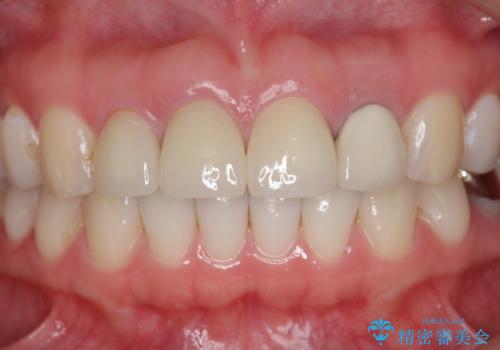

前歯の見た目を改善したい

- 前歯を天然の歯のようにきれいにやりかえたいと希望され来院されました。

審美的なジルコニアクラウンを装着し、審美性が回復されたと満足いただくことができました。